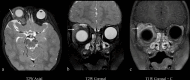

The lacrimal gland is a bilobed serous gland located in the superolateral aspect of the orbit. Lacrimal system pathologies can be broadly divided into pathologies of the lacrimal gland and those of the nasolacrimal drainage apparatus. These include distinct congenital, infectious, inflammatory, and benign, indeterminate, and malignant neoplastic lesions. Trauma and resultant fractures affecting lacrimal drainage apparatus is not part of this review; only non-traumatic diseases will be discussed. CT is the initial modality of choice because of its ability to delineate lacrimal system anatomy and demonstrate most lacrimal drainage system abnormalities and their extent. It also assesses bony architecture and characterizes any osseous changes. MRI is helpful in further characterizing these lesions and better assessing involvement of the surrounding soft tissue structures. In this pictorial review, we will review the anatomy of the lacrimal system, describe CT/MRI findings of the common and uncommon lacrimal system abnormalities and discuss relevance of imaging with regards to patient management.